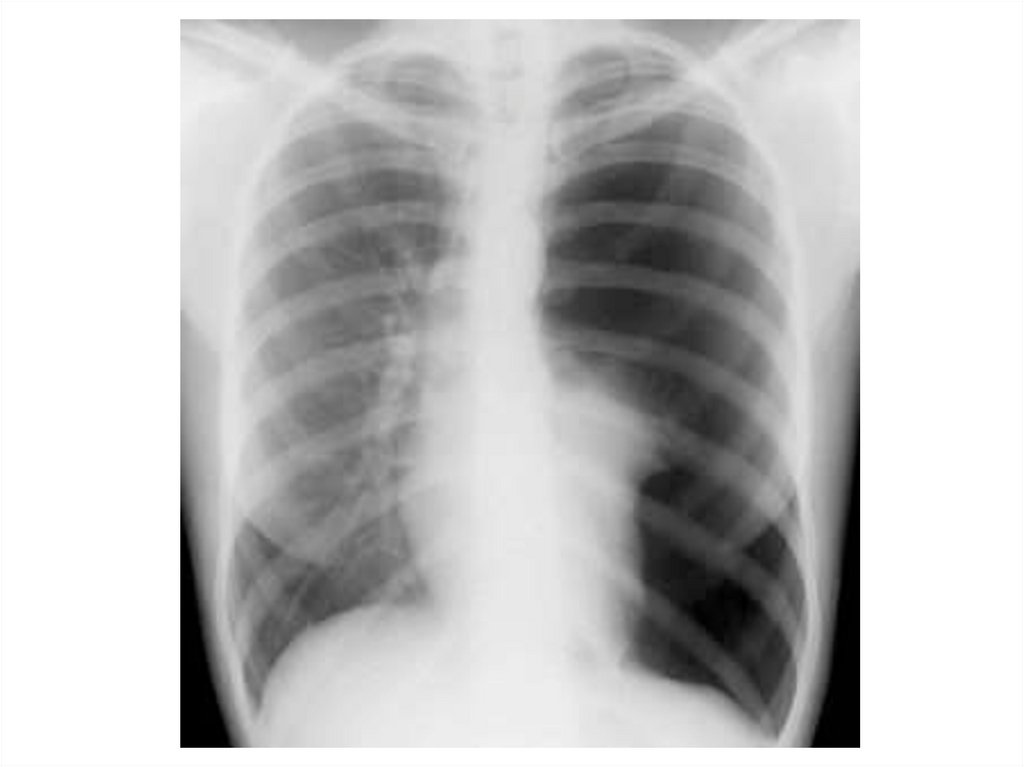

Воронкообразная деформация

грудной клетки

Индекс Хеллера

Индекс Гижицкой